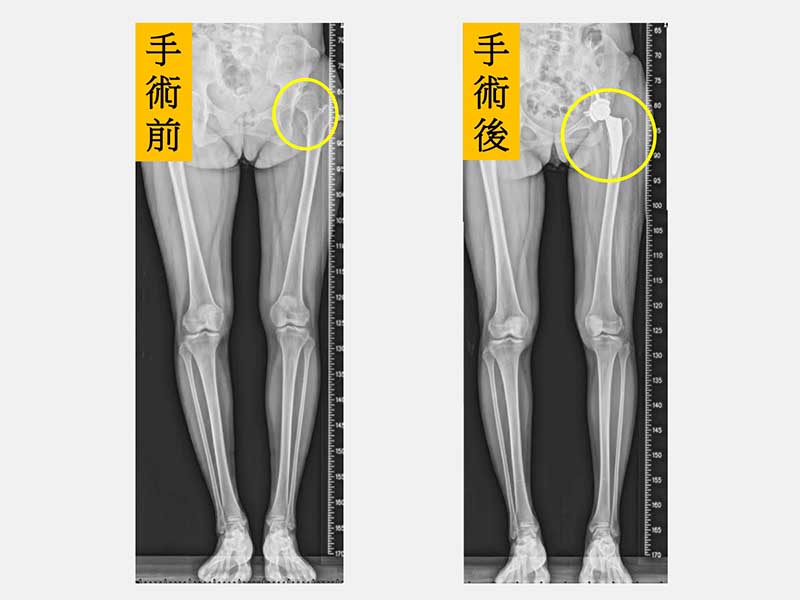

黃贊文部長表示,陳小姐因為長年疼痛和不能好好參加小孩的社團發表、學校活動讓她看起來非常憂鬱,也轉介給身心科醫師一同協助。陳小姐左側髖關節和大腿因為曾經手術2次有著長達30公分疤痕,肌肉也有明顯的萎縮,因此建議進行「微創正前開髖關節置換手術」。陳小姐在手術當天下午麻醉藥效一退,就開始練習騎腳踏車運動,陳小姐說,原本以為會很痛,但完全沒有痛的感覺,2隻腳也一樣長了,腳踩在地上的感覺非常不真實,就像是睡了一覺做了一個夢,很擔心萬一夢醒了怎麼辦?當下激動到眼角泛淚。

黃贊文醫師指出,髖關節發育不良導致的髖關節炎一般好發在40至55歲,女性居多。若在兒童時期就診斷出來,可進行髖關節截骨矯正手術來促使髖關節得以正常發育;若是在成年後發現有初期的髖關節炎也可以藉由髖關節截骨矯正手術來延緩置換人工關節的時間;但若已進展到末期,治療的方式則是直接安排人工髖關節置換手術。